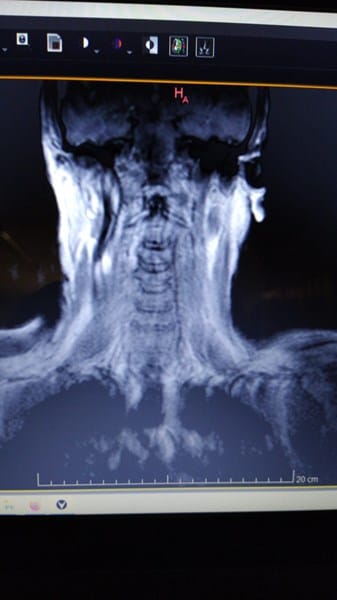

2/ Resonancia Magnética

Donde aparece espondiloartrosis con esclerosis de plataformas vertebrales y bordes ostofiticos

Osteartrosis en las articulaciones unciformes e interapofisiarias posteriores.

Discatrosis con baja señal de intensidad discal en secuencia T2

A nivel C3-4 Abombamiento discal paracentral y foraminal izquierdo

A nivel C4-5 Abombamiento discal con leve compromiso bilateral

A nivel C5-C6-C7 importantes abombamientos discales con compromiso bilateral-

Adjunto fotografias de la resonancia.